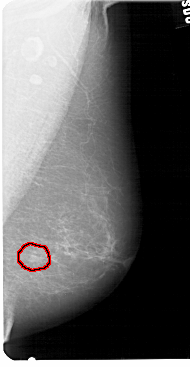

A_1428_1.RIGHT_CC

RIGHT_CC LINES 5491 PIXELS_PER_LINE 2611 BITS_PER_PIXEL 12 RESOLUTION 43.5 OVERLAY

FILE: A_1428_1.RIGHT_CC.OVERLAY

TOTAL_ABNORMALITIES 1

ABNORMALITY 1

LESION_TYPE MASS SHAPE LOBULATED MARGINS ILL_DEFINED

ASSESSMENT 4

SUBTLETY 4

PATHOLOGY BENIGN

TOTAL_OUTLINES 1

BOUNDARY